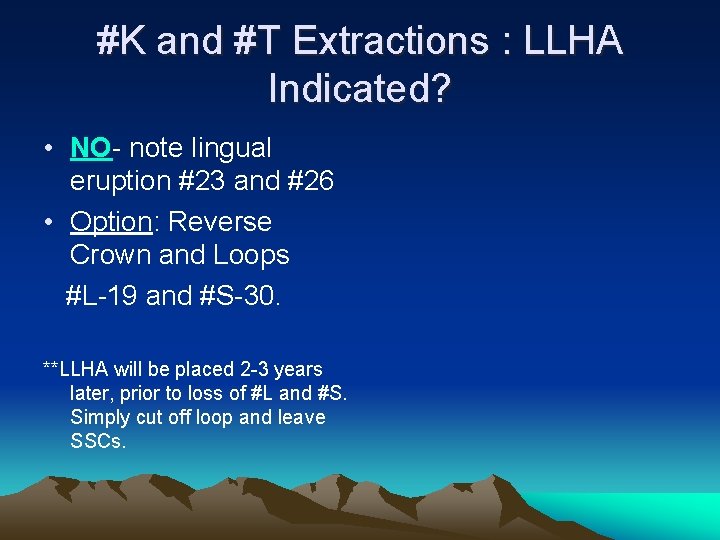

#K and #T Extractions : LLHA Indicated? • NO- note lingual eruption #23 and #26 • Option: Reverse Crown and Loops #L-19 and #S-30. **LLHA will be placed 2 -3 years later, prior to loss of #L and #S. Simply cut off loop and leave SSCs.